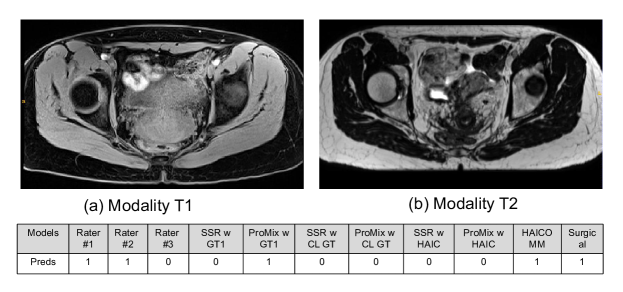

We also conduct qualitative analyses about HAICOMM. In Figure 2, (a) and (b) are the input T1 and T2 MRIs, respectively. The table below shows the predictions by the three raters (Rater #1,#2,#3), then the predictions by SSR and ProMix trained with Rater #1’s labels and CROWDLAB’s labels (SSR w GT1, ProMix w GT1, SSR w CL GT, ProMix w CL GT). Next, we show SSR and ProMix trained with CROWDLAB’s labels and relying on human-AI collaborative classification (SSR w HAIC, ProMix w HAIC), followed by the result from our HAICOMM, and the ground truth label from surgical data. The case shows the proposed HAICOMM model can generate correct labels while other models cannot. For Figure 3, the case also shows that the proposed HAICOMM model can generate a correct label while most other methods cannot (only ProMix w GT1 and HAICOMM predict the surgical ground truth label correctly).

Figure 2: Qualitative example analysis of HAICOMM.